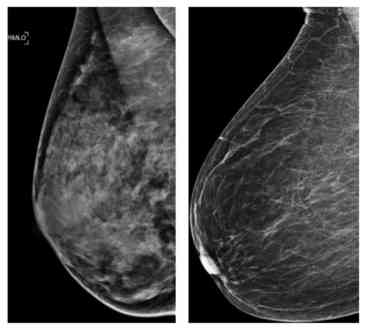

Standard mammograms typically take one image of each breast from two positions, while 3-D scans take several images of different layers of each breast. That allows for the detection of tumors that might be hidden under breast tissue and not noticeable on regular images, said Jim Culley, a spokesman for Hologic, which makes mammogram machines, including the combo ones used in the study that take both kinds.